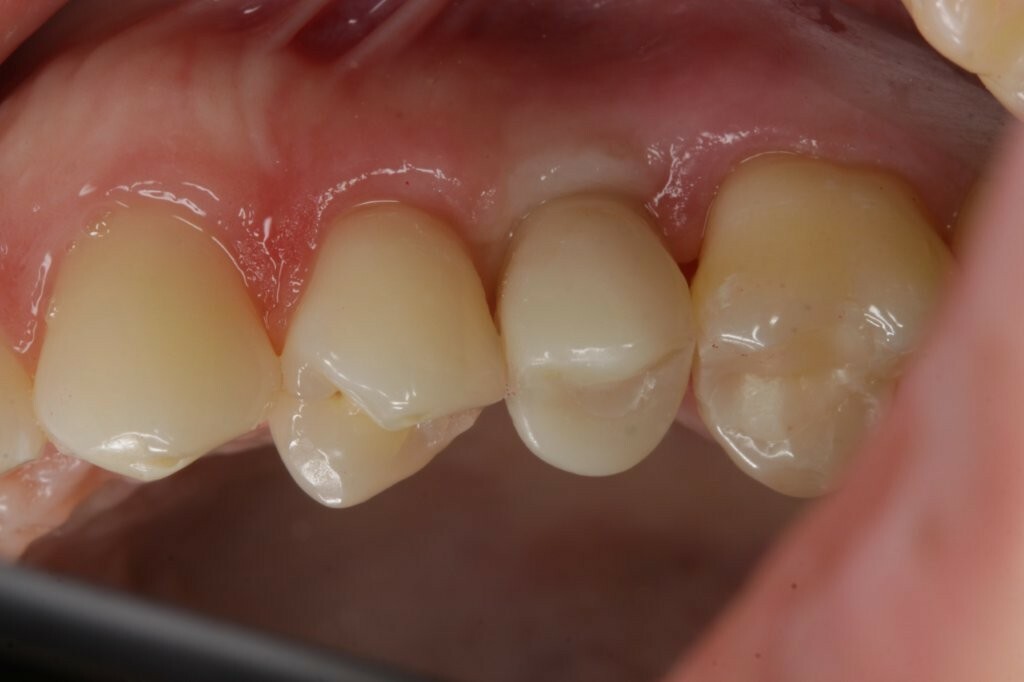

Ein Patient mit einem gepflegten Gebiss in eugnather Verzahnung (Abb. 1) stellte sich aufgrund einer Kronen-Wurzelfraktur an Zahn 25 in der Praxis vor. Die Untersuchung ergab, dass der Zahn aufgrund einer Fraktur des palatinalen Höckers mit subkrestalem Frakturverlauf (Abb. 2) nicht erhaltungswürdig war.